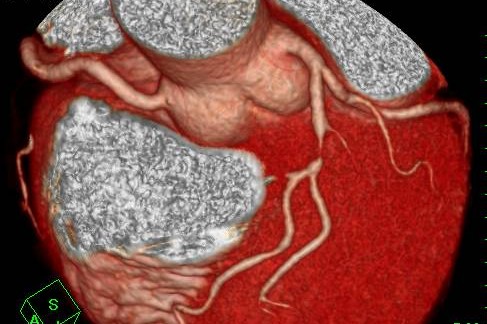

冠動脈CT(冠A-CT)検査について

当院では、冠動脈CT(冠A-CT)検査を行っております。

冠A-CT検査は、心臓の血管(冠動脈)をCTで詳しく調べる検査で、カテーテル検査の前段階として行える、体への負担が比較的少ない検査です。

冠動脈の狭窄(血管の狭くなり)や動脈硬化の状態を画像で確認することができ、自覚症状が出る前の早期の狭心症の発見や、将来の心筋梗塞のリスク評価(予知)に役立ちます。

画像検査

X線CT装置で心臓を画像化するという試みは以前からありましたが、検査のためには息止め時間が最短でも40秒と非常に長く、患者さんに大きな負担を与えてきました。導入されているCT装置は、世界で初めて心臓の検査(120mmのスキャン範囲)を8秒の息止め時間で可能にした装置ですので患者さんの負担を大幅に軽減することが可能です。また立体像(3次元画像)として撮影部を360度自由な方向から観察することが可能です。

このX線CTを使用することにより、従来の画像診断装置では困難であった無症状の心血管の狭窄(きょうさく:せまくなっている)を早期に発見したり、カテーテル治療(細い管を体内に挿入し、その先端を風船状に膨らませて心血管の狭窄部分を広げたりする治療)のフォローアップ検査装置として期待されています。